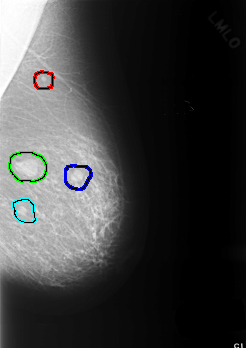

C_0364_1.LEFT_MLO

FILE: C_0364_1.LEFT_MLO.OVERLAY

TOTAL_ABNORMALITIES 4

ABNORMALITY 1

LESION_TYPE MASS SHAPE ROUND MARGINS CIRCUMSCRIBED

ASSESSMENT 2

SUBTLETY 5

PATHOLOGY BENIGN

TOTAL_OUTLINES 1

ABNORMALITY 2

LESION_TYPE MASS SHAPE OVAL MARGINS CIRCUMSCRIBED

ASSESSMENT 3

ABNORMALITY 3

LESION_TYPE MASS SHAPE LOBULATED MARGINS CIRCUMSCRIBED

ABNORMALITY 4